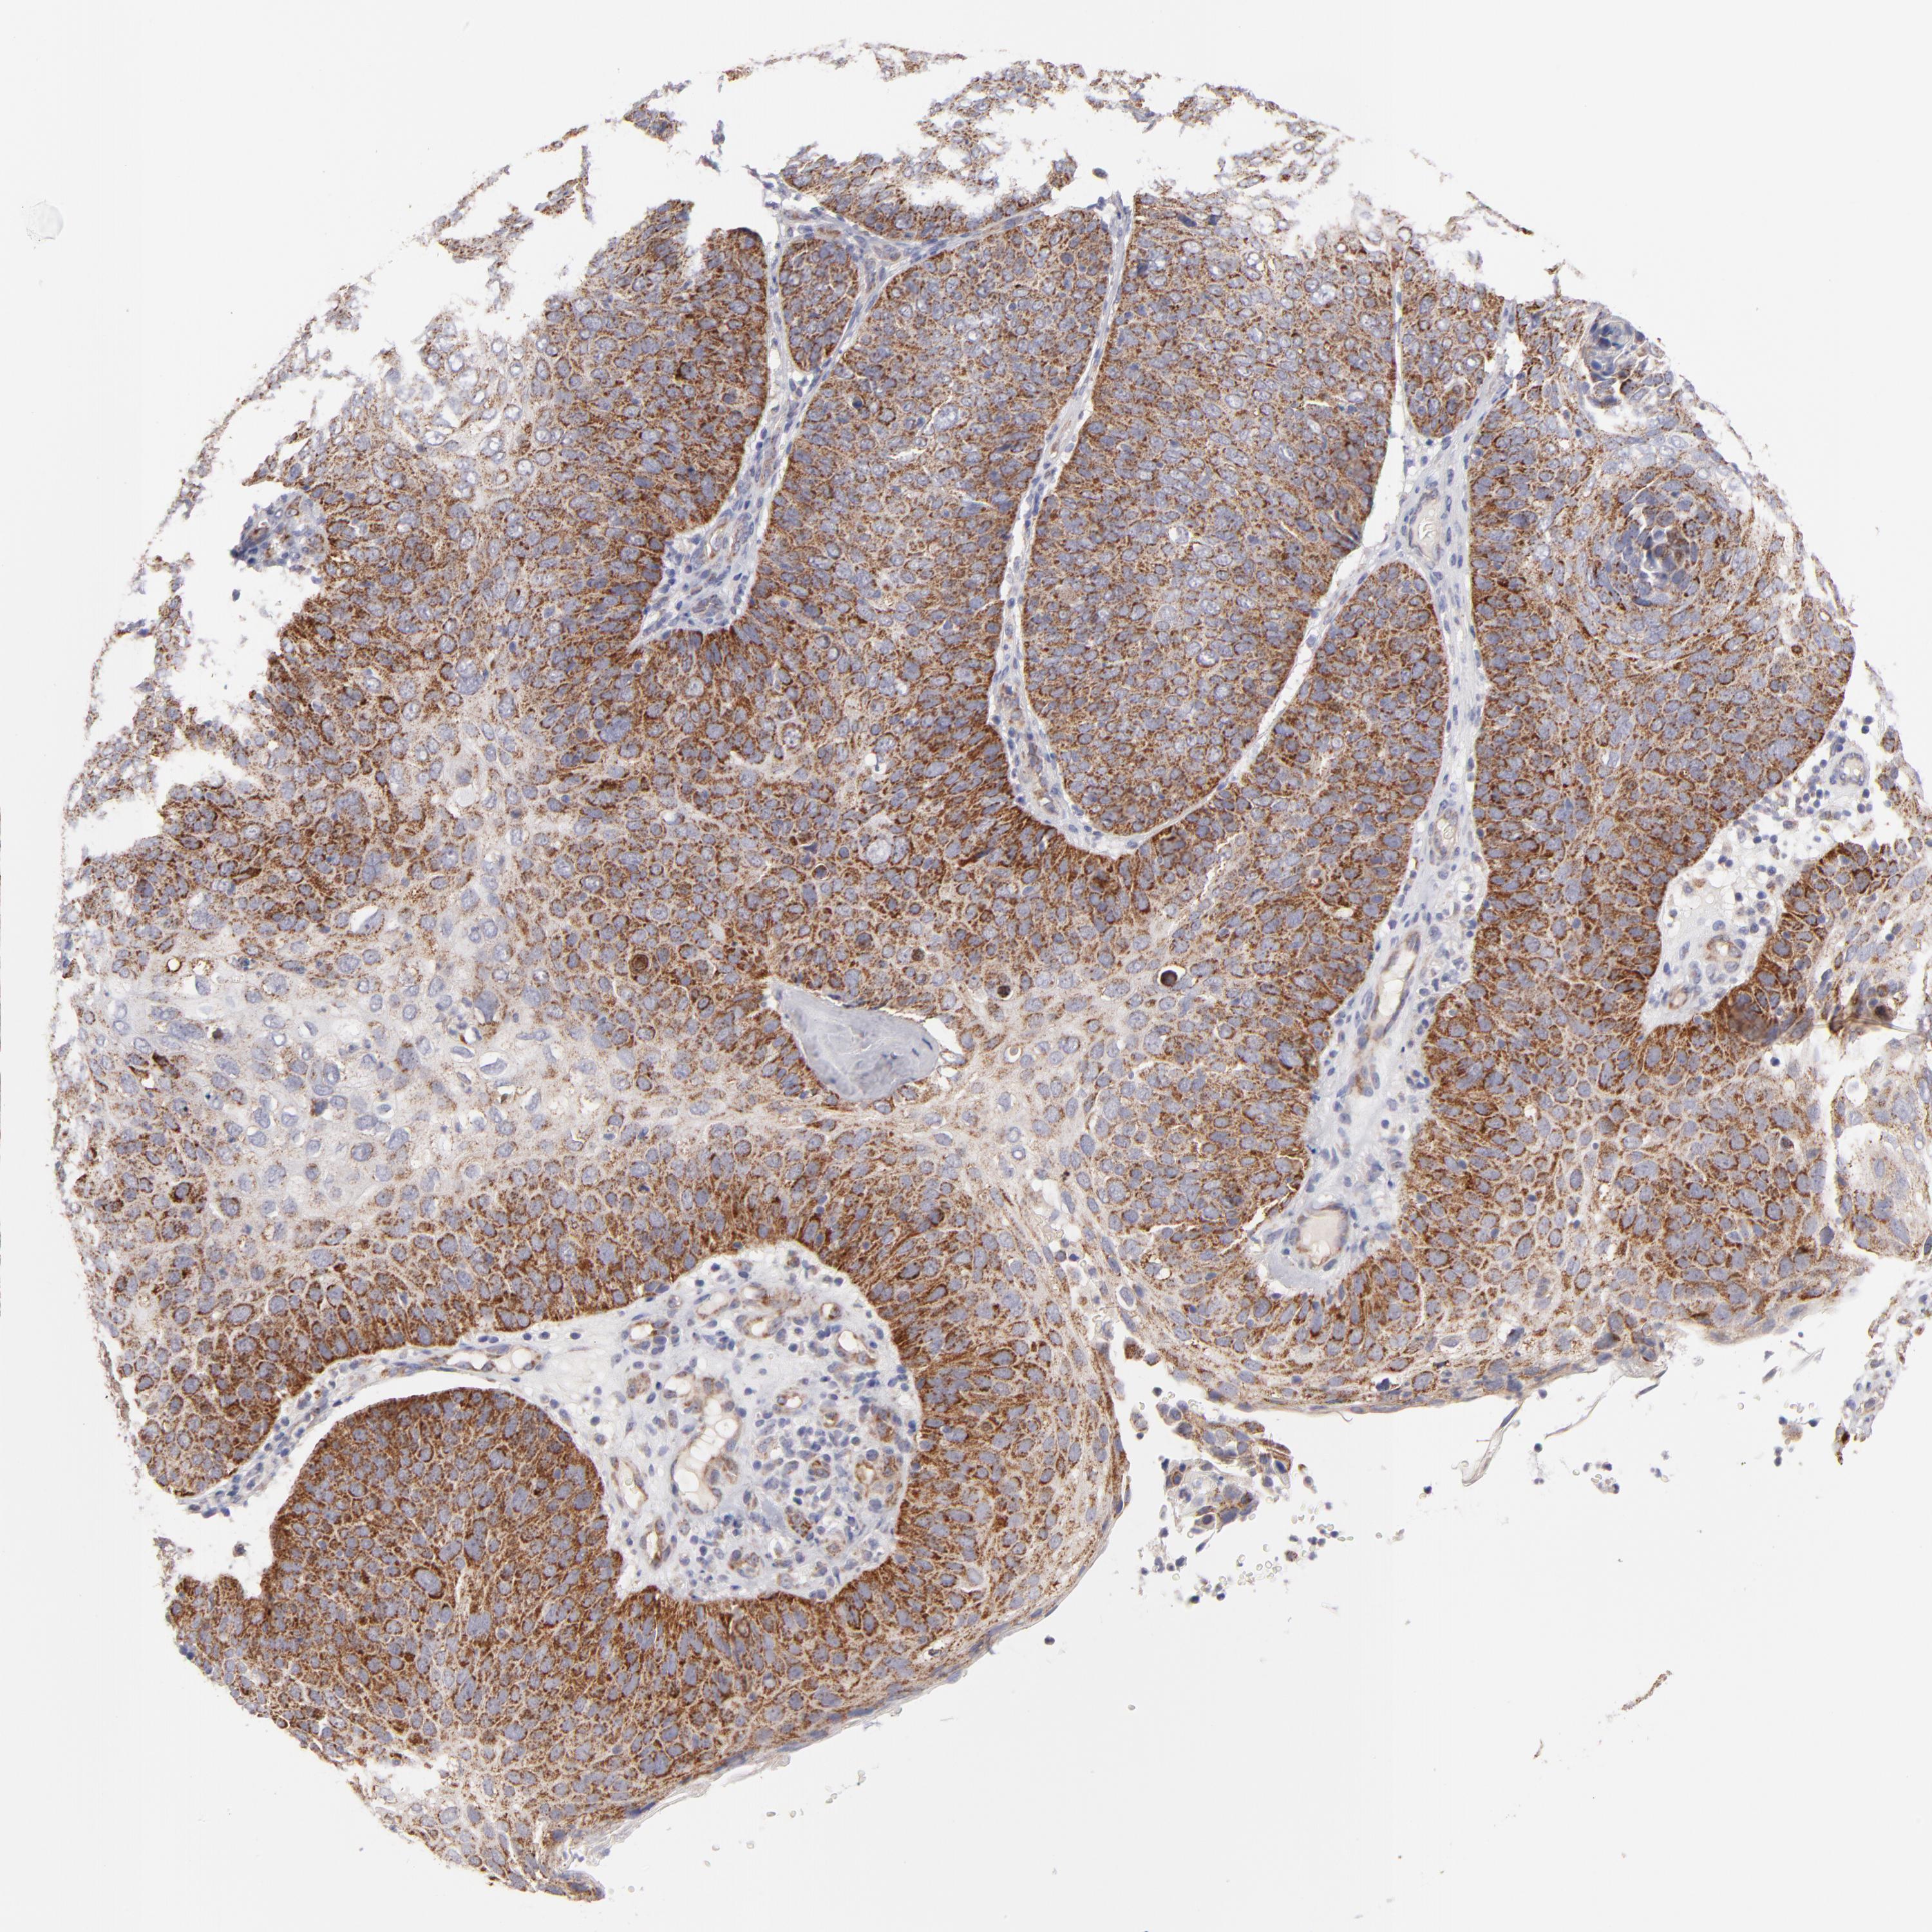

SKIN CANCER - Protein expressioni

A mouse-over function shows sample information and annotation data. Click on an image to view it in a full screen mode. Samples can be filtered based on level of antibody staining by selecting one or several of the following categories: high, medium, low and not detected. The assay and annotation is described here.

Antibody stainingi

Antibody staining in the annotated cell types in the current human tissue is reported as not detected, low, medium, or high, based on conventional immunohistochemistry profiling in selected tissues. This score is based on the combination of the staining intensity and fraction of stained cells.

Each image is clickable and will lead to virtual microscopy that enables deeper exploration of all samples and also displays staining intensity scores, fraction scores and subcellular localization as well as patient and tissue information for each sample.

Antibody HPA002946

Staining

High

Strong

>75%

Cytoplasmic/membranous

Squamous cell carcinoma, NOS

Basal cell carcinoma